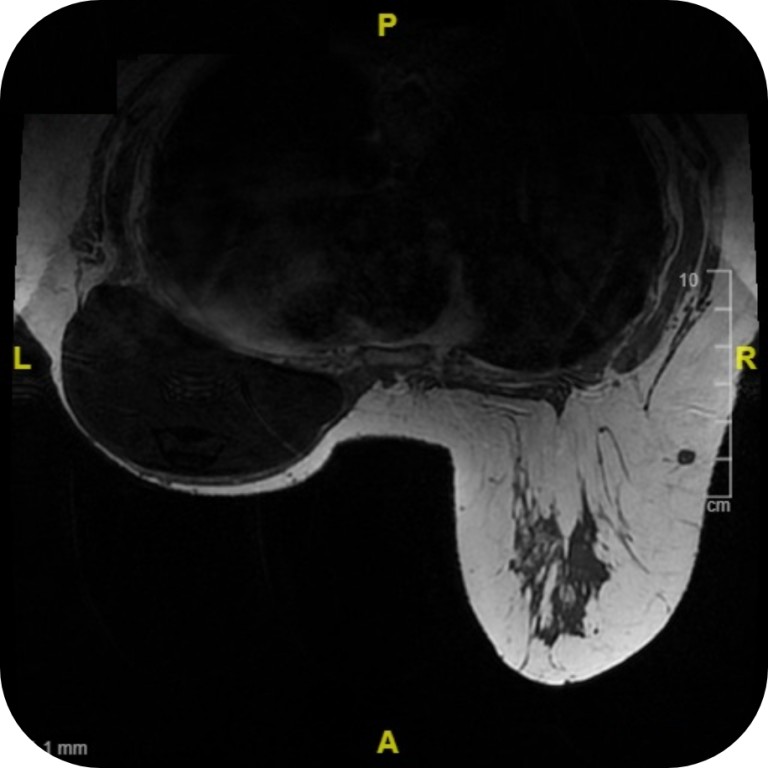

The Motiva Flora® SmoothSilk® Tissue Expander images at high field (3T).

MRI with Motiva Flora® SmoothSilk® Tissue Expander with RFID Port

Motiva Flora® SmoothSilk® Tissue Expanders with the RFID port do not generate distortion of T1 (a) or T2 (b) in weighted axial MRI images*.

MRI with Traditional Magnetic Port

Traditional magnetic ports create large distortions that impede correct assessment of T1 (a) and T2 (b) in weighted axial MRI images, even in the contralateral breast*.